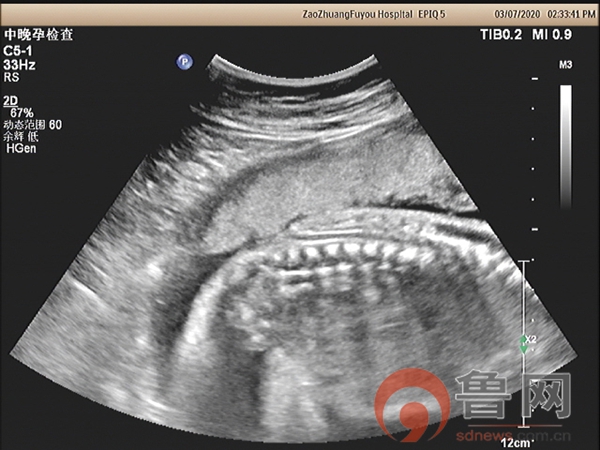

图2:脊髓圆锥低位并局部皮肤缺损

图3骶尾部皮肤连续性中断

该孕妇在18孕周唐筛提示神经管缺陷高风险,又进行了无创DNA检查未见染色体异常,18孕周时外院超声检查未发现明显异常,26孕周+时外院因胎儿“小脑显示异常”转枣庄市妇幼保健院超声科会诊。超声检查显示胎儿头颅呈“柠檬头”状,小脑呈“香蕉状”并后颅窝池消失,枣庄市妇幼保健院具有丰富产前超声筛查经验的超声科专家马上意识到,此例胎儿的头部与小脑形态异常,是“开放性脊柱裂”胎儿头部异常的伴发征象。遵循这个思路,随后仔细扫查胎儿脊椎骨,发现脊髓圆锥位置低于腰4以下,骶尾部皮肤回声中断,胎儿脊柱椎体排列尚规则,脊柱无侧弯,无后凸,做出了“开放性脊柱裂”的最终诊断。该例胎儿脊柱的超声异常征象表现细微,远远不如间接征象表现明显,对于经验不足的年轻超声医师极其容易漏诊,因此对本病例诊断过程提出以下思考: